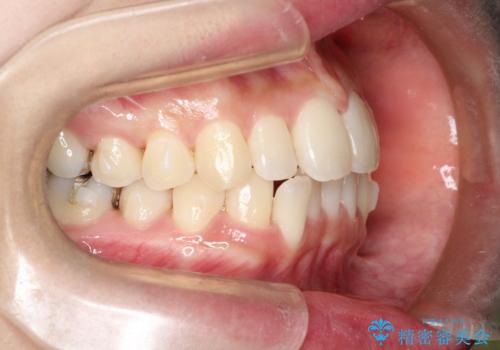

初診時の歯並びの状態としては、上下ともに前歯部の中等度のがたつきがあり、特に左上の前歯が1本内側に入り込んでしまっている状態でした。

内側に入り込んでしまっている歯を出してくることに非常に時間がかかりましたが、一度歯を歯茎の方へ押し込みそして前へ出してくる2段階の治療を行いました。

見た目、噛み合わせ及び、治療期間や施術内容に大変ご満足いただきました。